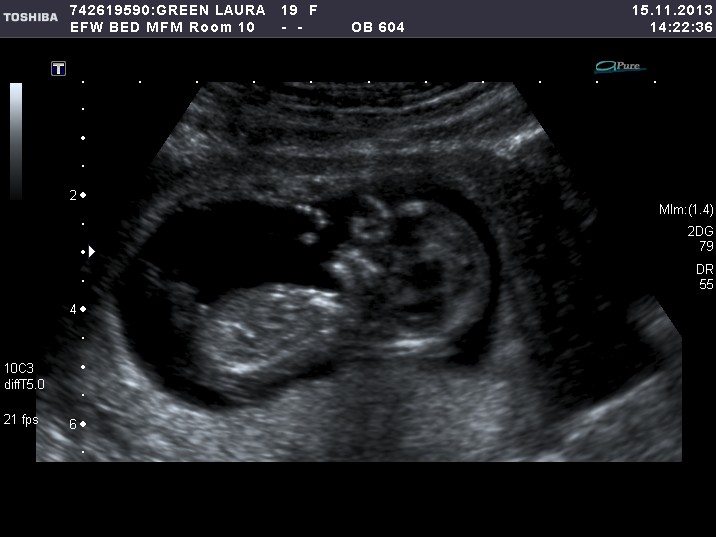

Thanks everyone! Heres the only pic of the nub. Does that look like a boy? I'm really torn about what I see. At first I thought it was a boy but then the utrasound tech kept say "such a pretty baby" which made me start to think it might be a girl. Then I looked at the nub and it was hard to tell.... Anymore thoughts? Sure appreciate your feedback. :flowerz:

Boy